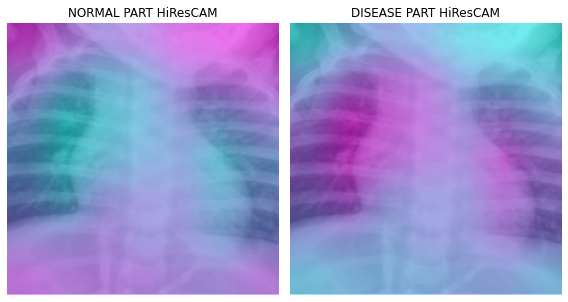

fig, (ax1,ax2) = plt.subplots(1,2)

dls.train.decode((x,))[0].squeeze().show(ax=ax1)

ax1.imshow(-cam_hirescam.squeeze(),alpha=0.5,extent=(0,224,224,0),interpolation='bilinear',cmap='cool')

ax1.set_title("NORMAL PART HiResCAM")

#

dls.train.decode((x,))[0].squeeze().show(ax=ax2)

ax2.imshow(cam_hirescam.squeeze(),alpha=0.5,extent=(0,224,224,0),interpolation='bilinear',cmap='cool')

ax2.set_title("DISEASE PART HiResCAM")

fig.set_figwidth(8)

fig.set_figheight(8)

fig.tight_layout()